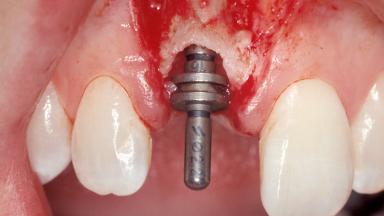

A 30-year-old female patient was referred to the office for the treatment of tooth 11. Her chief concern at the initial visit was to inquire, “Why is my tooth pink?” Upon clinical examination, it was determined that tooth 11 had a previous history of trauma and that the clinical crown had become noticeably pink in color as a result of internal resorption. This diagnosis was confirmed radiographically, indicating a large radiolucency involving the central and distal portions of the clinical crown. It was determined that restoration of this tooth was not possible, and that extraction was indicated. The presence of a mid-line diastema, which the patient wanted to reproduce, directed the treatment plan for tooth replacement utilizing a dental implant.

Type of Implants One-Piece|Reduced-Diameter

Placement Protocol Immediate implant placement

Tooth Site Maxillary incisor or canine

Socket Morphology Single-root socket